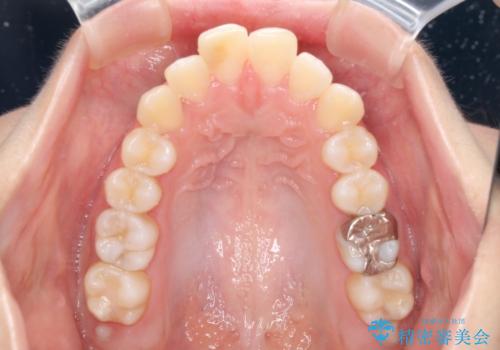

突出した口元が気になる ハーフリンガル装置による抜歯矯正

- 口元の突出感を気にして来院された患者様です。

通常では上下左右の第一小臼歯4本を抜歯しますが、下顎が左側にシフトしていたため、下顎左側のみ第二小臼歯を抜歯し、正中を合わせながら口元を下げる治療計画としました。